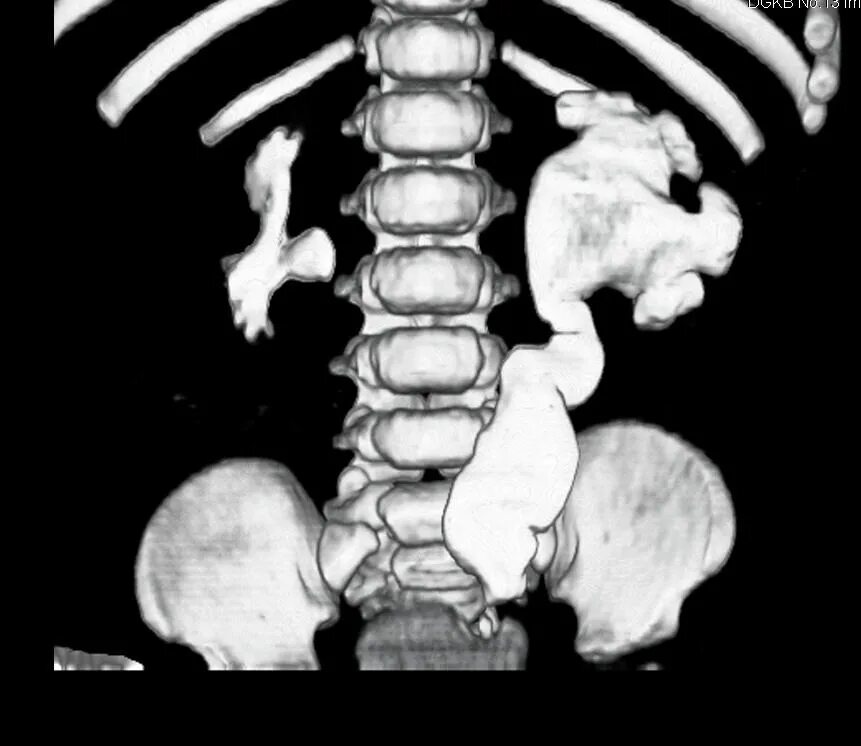

Мегауретер у детей что это